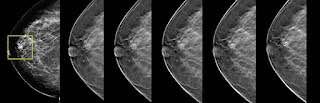

В отделении лучевой диагностики №2 выполняется усовершенствованное обследование молочных желез – маммография с томосинтезом. Маммография является обязательных скрининговым обследованием молочных желез после 40 лет для раннего выявления патологических изменений.

Классическая маммография обычно выполняется в двух взаимоперпендикулярных проекциях, а функция томосинтеза позволяет получать серию послойных изображений, которые делаются с промежутком от 1 мм до 5 мм и затем объединяются в одну трехмерную картину. При необходимости можно рассмотреть каждое из послойных изображений отдельно, в результате чего повышается эффективность выявления узловых образований, которые могут быть незаметны на обычной маммографии и при плотной ткани молочной железы, при этом лучевая нагрузка остается минимальной.